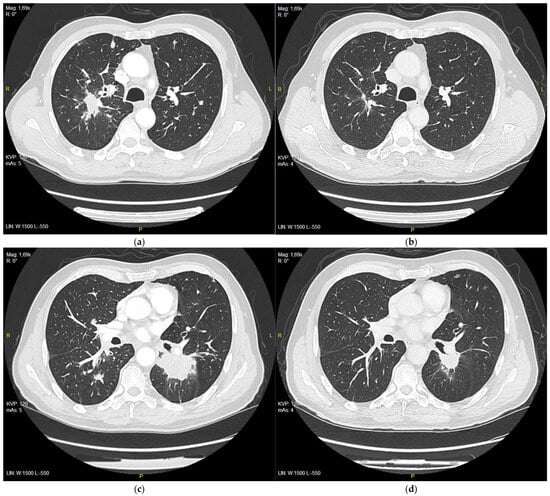

After 3 months of treatment, CT evaluation was performed by RECIST 1.1 and a partial response was observed, with a reduction in target lesions from 111 mm to 59 mm (Figure 2a–d).

Figure 2. (a) Right upper lobe nodule at the initiation of the treatment with erlotinib, 28 mm in diameter; (b) right upper lobe nodule after 3 months of treatment, 11 m in diameter; (c) tumor in 6th segment of left lung at the initiation of the treatment with erlotinib, 51 mm in diameter; (d) tumor after 3 months of treatment, 25 mm in diameter.